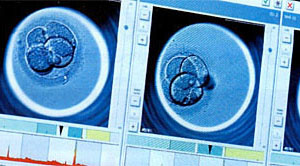

EmbryoScope +™は内部に顕微鏡とカメラを備えたタイムラプス培養器です。約10分に1回受精卵の撮影を行い、その様子は、受精卵を外に出さなくても付属のモニターで観察することができます。

実際に胚の分割から胚盤胞までの過程を映像としてご覧になることができます。